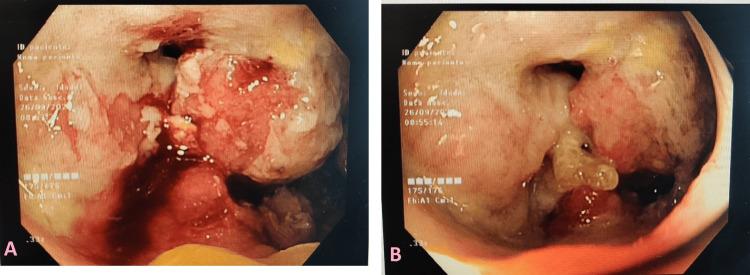

Celiac disease (CD) is an autoimmune disease triggered by gluten in the diet. The association between CD and increased risk of neoplasia is described mainly in patients diagnosed with CD and aged over 40 years or during the first years after CD diagnosis. Patients who remain symptomatic after 12 months of gluten-free diet should be screened to exclude neoplasms, especially lymphoma and gastrointestinal neoplasms. We report a case of small bowel adenocarcinoma (SBA) in a patient diagnosed with CD one year earlier.

乳糜泻(CD)是一种由饮食中的麸质引发的自身免疫性疾病。CD与肿瘤发生风险增加之间的关联主要见于年龄超过40岁的CD确诊患者或CD确诊后的最初几年。无麸质饮食12个月后仍有症状的患者应进行筛查以排除肿瘤,尤其是淋巴瘤和胃肠道肿瘤。我们报告一例小肠腺癌(SBA)病例,该患者一年前被诊断为CD。